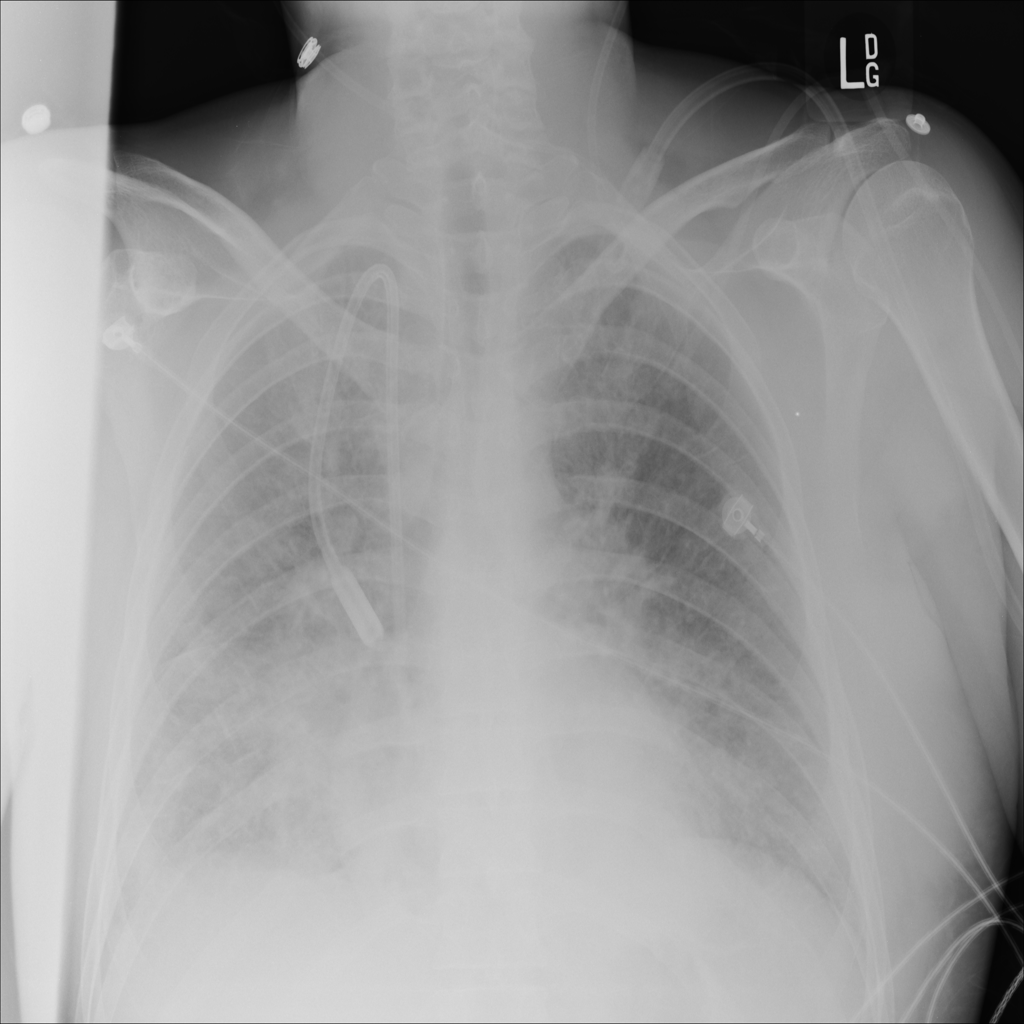

PAT-E828 · IMG-004Edema

PAT-E828 · IMG-004

AP